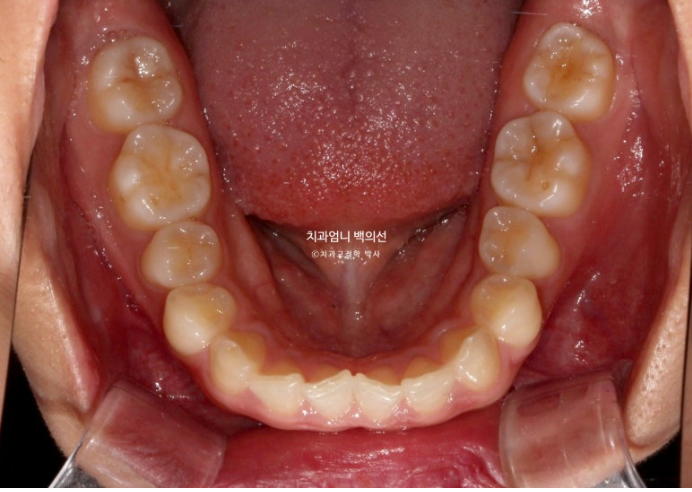

과개교합 옥니 거미스마일 치료 설명드리겠습니다.

오늘은 앞니가 깊게 물리는 과개교합과 거미스마일이 있을 때 인비절라인 라이트로 단기간에 어떤 것을 할 수 있는 지 보여드리겠습니다.

24년 3월 잇몸성형을 위해 오신 분입니다.

위 앞니 4개가 전반적으로 짧은 편이고 웃을 때 잇몸이 많이 보이는 거미스마일이 있습니다.

잇몸성형으로 거미스마일을 어느정도는 해결할 수 있지만 앞니가 뒤로 쓰러진 옥니이고 깊게 물리는 과개교합도 있고 앞니 사이도 벌어져 있어서 교정을 권유드렸습니다.

어금니교합은 좋습니다.

위 앞니가 아래 앞니를 깊게 덮어 아래앞니가 전혀 보이지 않는 정도의 심한 과개교합입니다.

위 앞니는 정상각도보다 뒤로 쓰러진 옥니입니다

앞니 사이사이에 벌어진 틈도 있습니다.